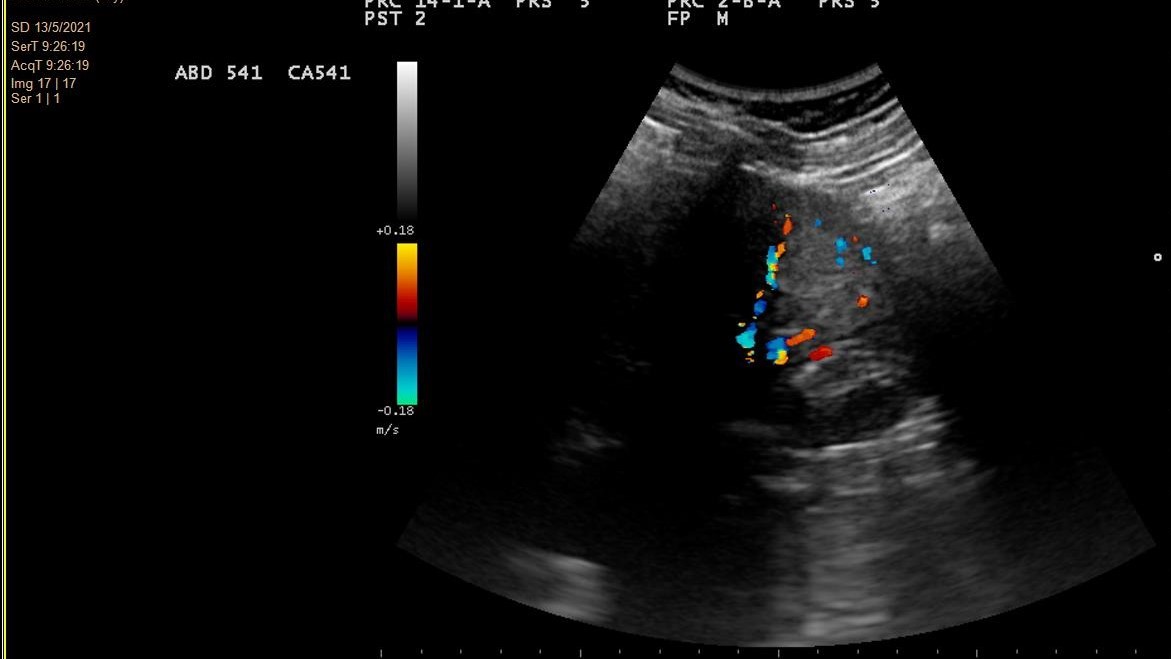

- Hallazgos ecográficos (mayo 2021): Imagen hiperecogénica redondeada de 2,9 cm de diámetro, de ecogenicidad irregular, localizada en tercio medio-distal del riñón derecho, sin evidenciarse litiasis o hidronefrosis.